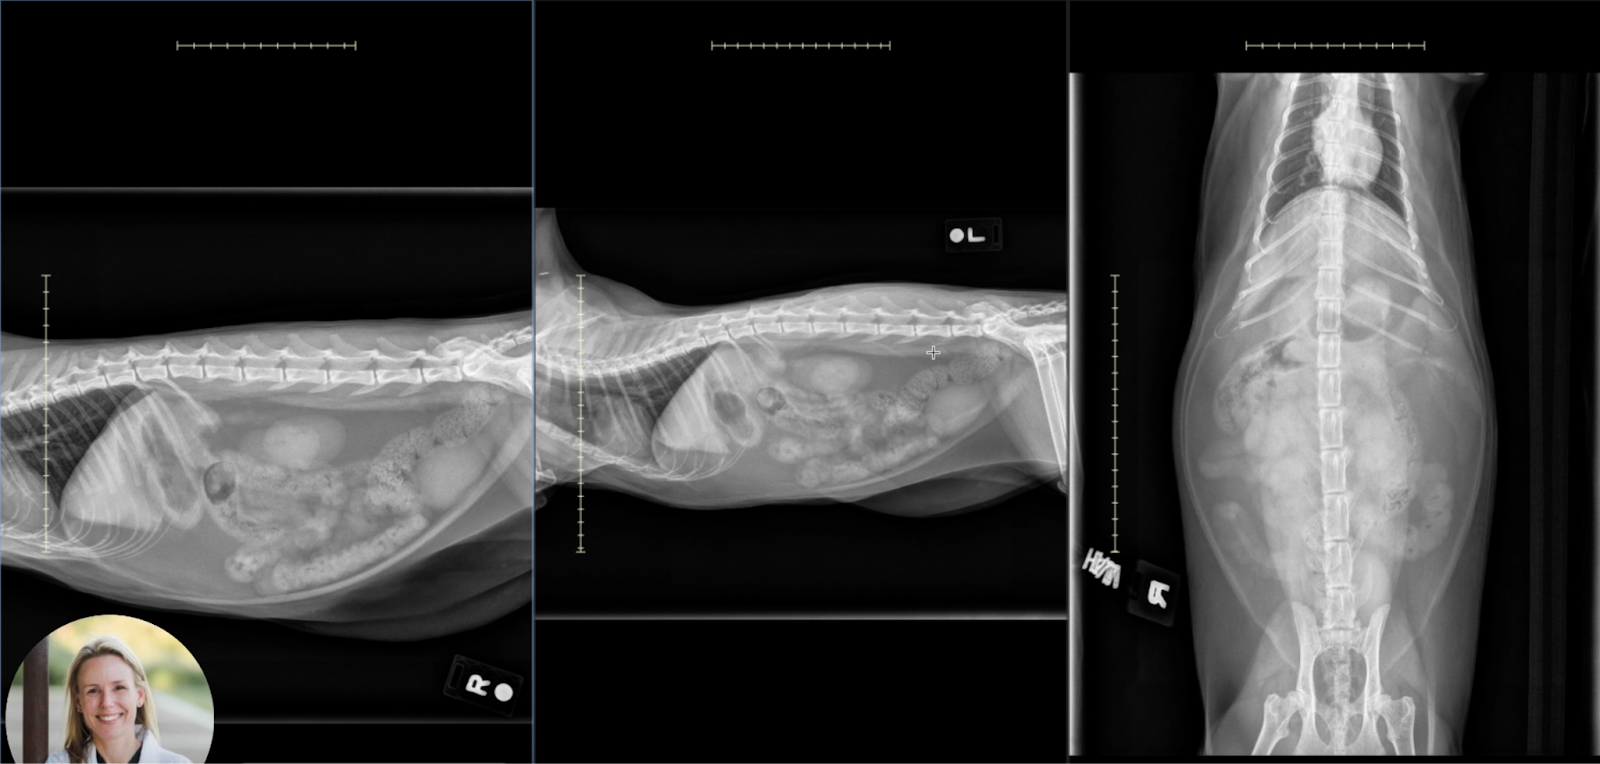

Image 4: Composite Overview

This comparison of orthogonal views highlights:

• Global plication with accordion-like narrowing of the small intestines.

• Fragmentation of gas bubbles, discontinuous lucency, and poor distinction between adjacent loops.